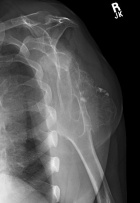

68 yo male with complaints of right shoulder pain with repetitive activities and modified with rest. History of multiple orthopaedic surgeries in the past. He denies history of trauma or constitutional symptoms.

PE: Elderly male in good overall health. Short stature. Palpable mass in posterior right shoulder. Nontender w/o edema or overlying skin changes. Limited ROM in all dimensions. NVI w/o LAN.